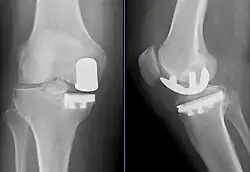

Knieprothese

Eine Knieprothese, Knieendoprothese oder Kniegelenksprothese ist eine implantierte Prothese (Endoprothese), die das Kniegelenk ganz (als TEP = Totalendoprothese) oder teilweise ersetzt. Die Knieprothese wird hauptsächlich bei schwerem Verschleiß des Knies (Kniegelenksarthrose = Gonarthrose, Pangonarthrose) und nach Verletzungen des Knies als operative Therapie eingesetzt, um die schmerzfreie Bewegungsfähigkeit und gegebenenfalls bei Bandinstabilitäten zusätzlich auch die Kniegelenksstabilität wiederherzustellen. Es können Teil- oder Totalendoprothesen (als Halb- oder Ganzgelenke) verwendet werden. Die Knieprothese ist nach der Hüftgelenksprothese die am zweithäufigsten verwendete Gelenksendoprothese mit deutschlandweit jährlich etwa 175.000 Erst-Operationen (Erstimplantationen 2009).[1]

Das sogenannte Uniknie (unikondyläre (syn. monokondyläre) Schlittenprothese) kommt zur Anwendung, wenn alle Bänder am Kniegelenk voll funktionsfähig sind und nur an einem der beiden Kondylen eine Schädigung des Gelenkknorpels vorliegt. Während die Komponente femoral uniform aus einer Metalllegierung besteht, existieren tibial drei verschiedene Grundtypen: reine Polyethylenkomponente (sog. all-poly, z. B. Genesis, Journey, Mod I, St. Georg, UC plus), fest fixierte PE-Komponente mit Metallbasis (sog. metal-backed, z. B. Genesis, Journey, Mod II, UC Plus) oder analoge Varianten mit mobiler PE-Komponente (z. B. Oxford, LCS uni). Eine bikondyläre Primärprothese kann zum Einsatz kommen, wenn mindestens zwei der drei Gelenkabschnitte (inneres bzw. äußeres Kompartment sowie Kniescheibe mit Gleitlager) und ggf. auch das vordere Kreuzband beschädigt sind, die anderen Bänder aber ausreichend funktionsfähig sind. Es werden sowohl am Oberschenkelknochen als auch am Schienbein die Gelenkflächen ersetzt. Die Menisken werden entfernt. Es gibt auch einzelne Implantatsysteme, die selbst bei intaktem vorderem Kreuzband eingesetzt werden können.

Bei den primären Totalendoprothesen erfolgt eine Einteilung der Prothesen in der Regel danach, ob die Kreuzbänder erhalten werden, dann wird eine CR-Prothese (cruciate retaining ‚Kreuzband-erhaltende Prothese‘) eingesetzt. Sind die Kreuzbänder nicht erhalten oder werden sie im Rahmen der Operation entfernt, wird eine Prothese verwendet, die die Funktion der Kreuzbänder teilweise übernimmt. Dies ist eine PS-Prothese (posterior stabilised ‚posterior stabilisierte Prothese‘). Diese führt das Schienbein bei zunehmender Beugung nach vorne bzw. den Oberschenkelknochen nach hinten.